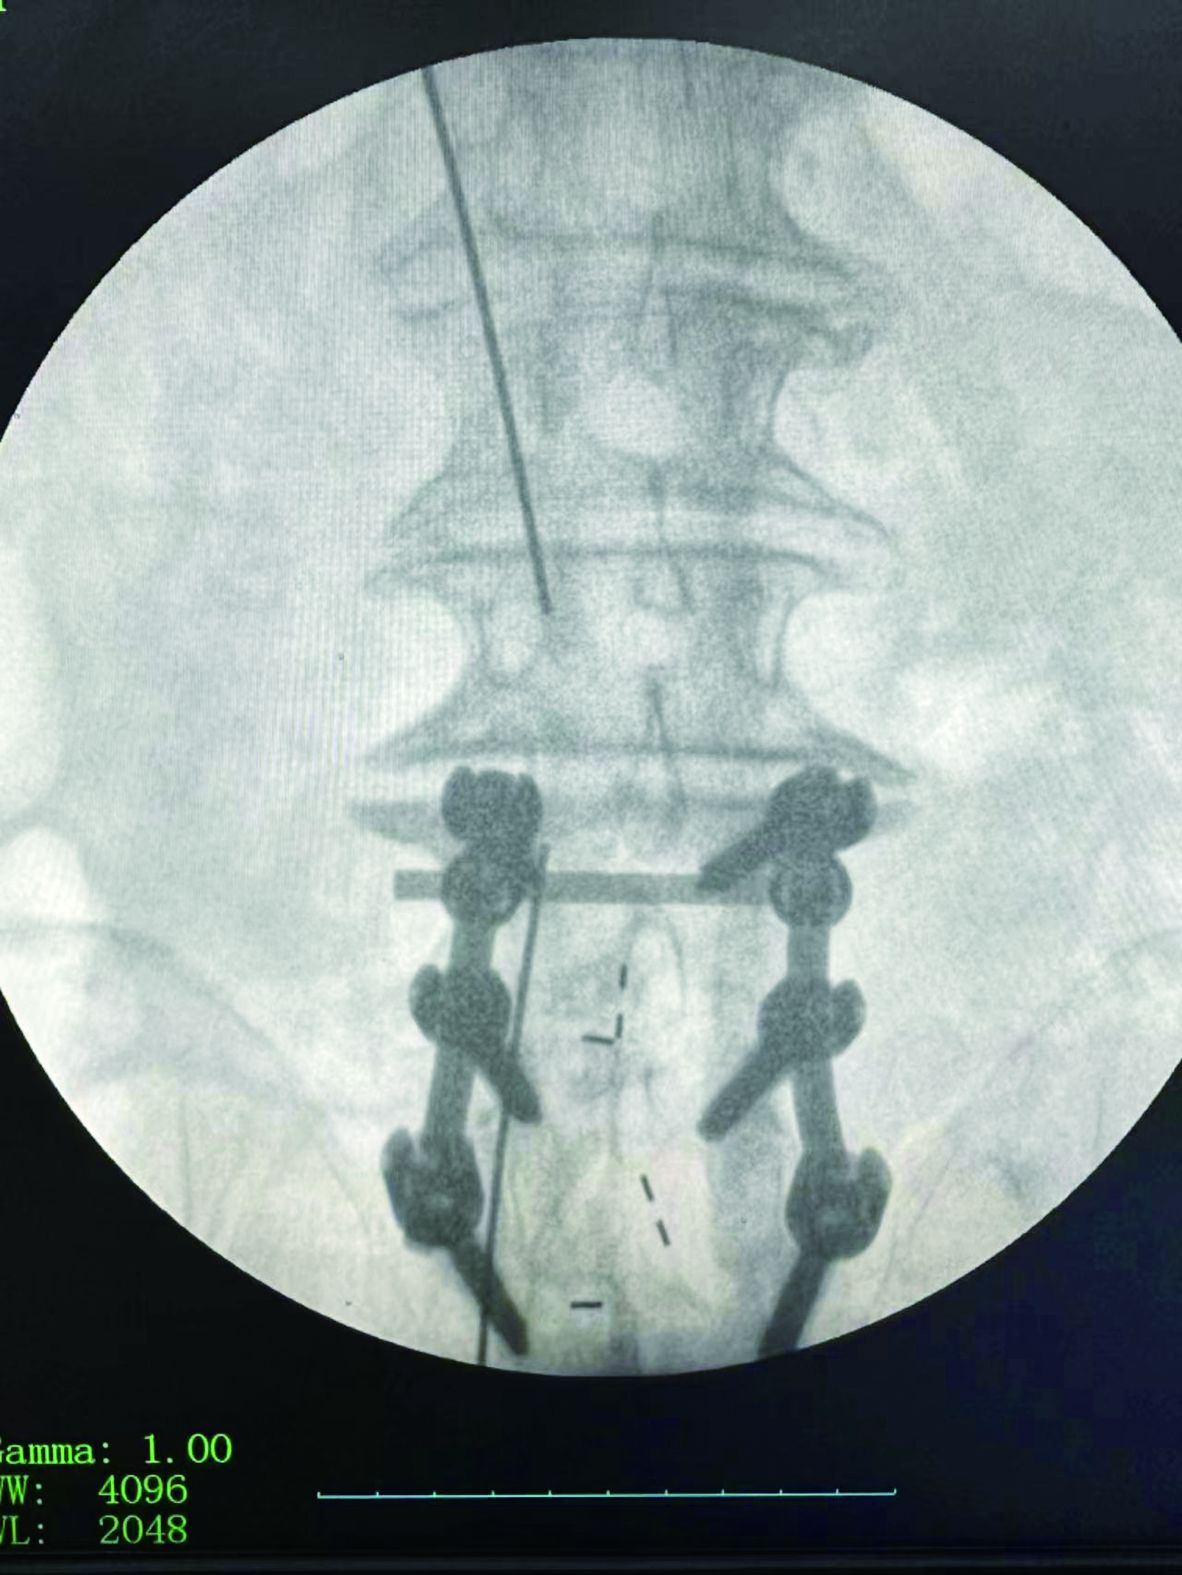

▲術(shù)中定位

近日,李建偉在黔江區(qū)中醫(yī)院骨科團(tuán)隊緊密配合下,成功為6位老年患者實施(UBE)脊柱內(nèi)鏡下椎間盤摘除、椎管減壓術(shù)。目前患者康復(fù)效果良好,手術(shù)的成功開展,標(biāo)志著黔江區(qū)中醫(yī)院在(UBE)脊柱內(nèi)鏡技術(shù)上有了新的突破。

據(jù)了解,患者楊爺爺今年70歲,因腰部及左下肢疼痛10天入院,入院時查體,左側(cè)大小腿壓痛,直腿抬高試驗陽性,感覺減退,肌力無減退。CT及MRI提示:腰3-4椎間盤突出、椎管狹窄,入院后經(jīng)正規(guī)保守治療2周,腰部及左下肢疼痛無緩解。為盡快緩解患者癥狀,達(dá)到早日康復(fù)目標(biāo),李建偉和骨科團(tuán)隊進(jìn)行了周密的術(shù)前討論和規(guī)劃,決定舍棄傳統(tǒng)手術(shù)方案,為患者制定了“UBE(單側(cè)雙通道脊柱內(nèi)鏡技術(shù))下椎管減壓、椎間盤髓核摘除”微創(chuàng)治療方案。

經(jīng)過精密的術(shù)前準(zhǔn)備,術(shù)中使用UBE專用器械和等離子射頻手術(shù)系統(tǒng),視野清晰,操作靈活,椎板減壓,在保護(hù)神經(jīng)根和硬膜囊的前提下輕松摘除脫出的椎間盤髓核,與傳統(tǒng)手術(shù)相比,該手術(shù)方式兼具微創(chuàng)、安全、有效、并發(fā)癥少等顯著優(yōu)勢,病人背部只有兩個2cm的小切口。患者術(shù)后腰腿疼痛癥狀消失,術(shù)后第二天即可下床行走,手術(shù)效果顯著,得到了患者及家屬的高度認(rèn)可。